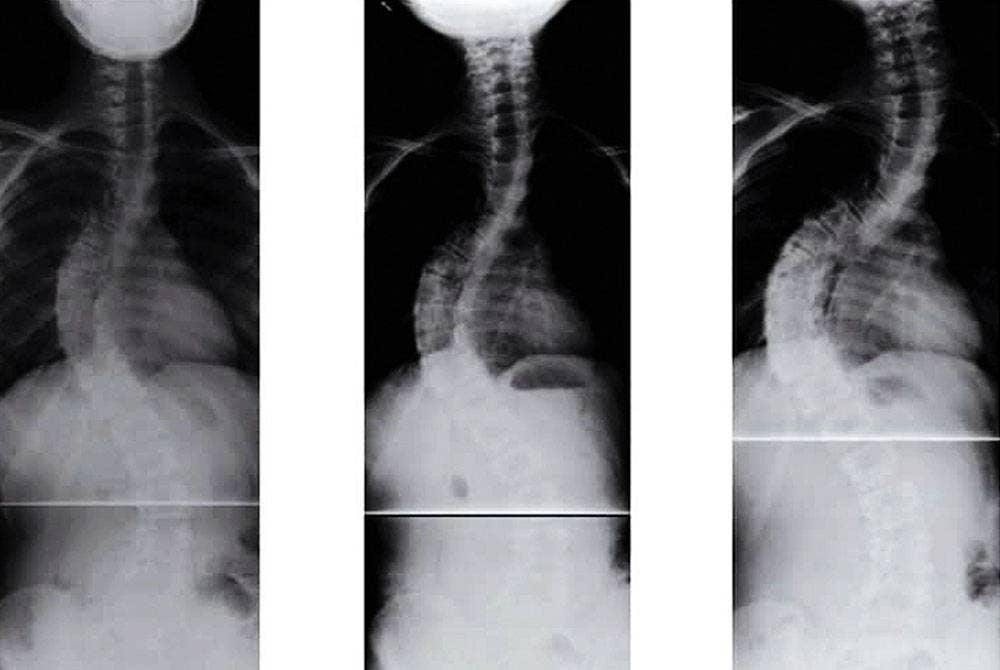

Menggalas beg berat sehingga menyebabkan sakit belakang itu dikategorikan sebagai Postural atau ‘Non-structural Scoliosis’ yang bersifat sementara